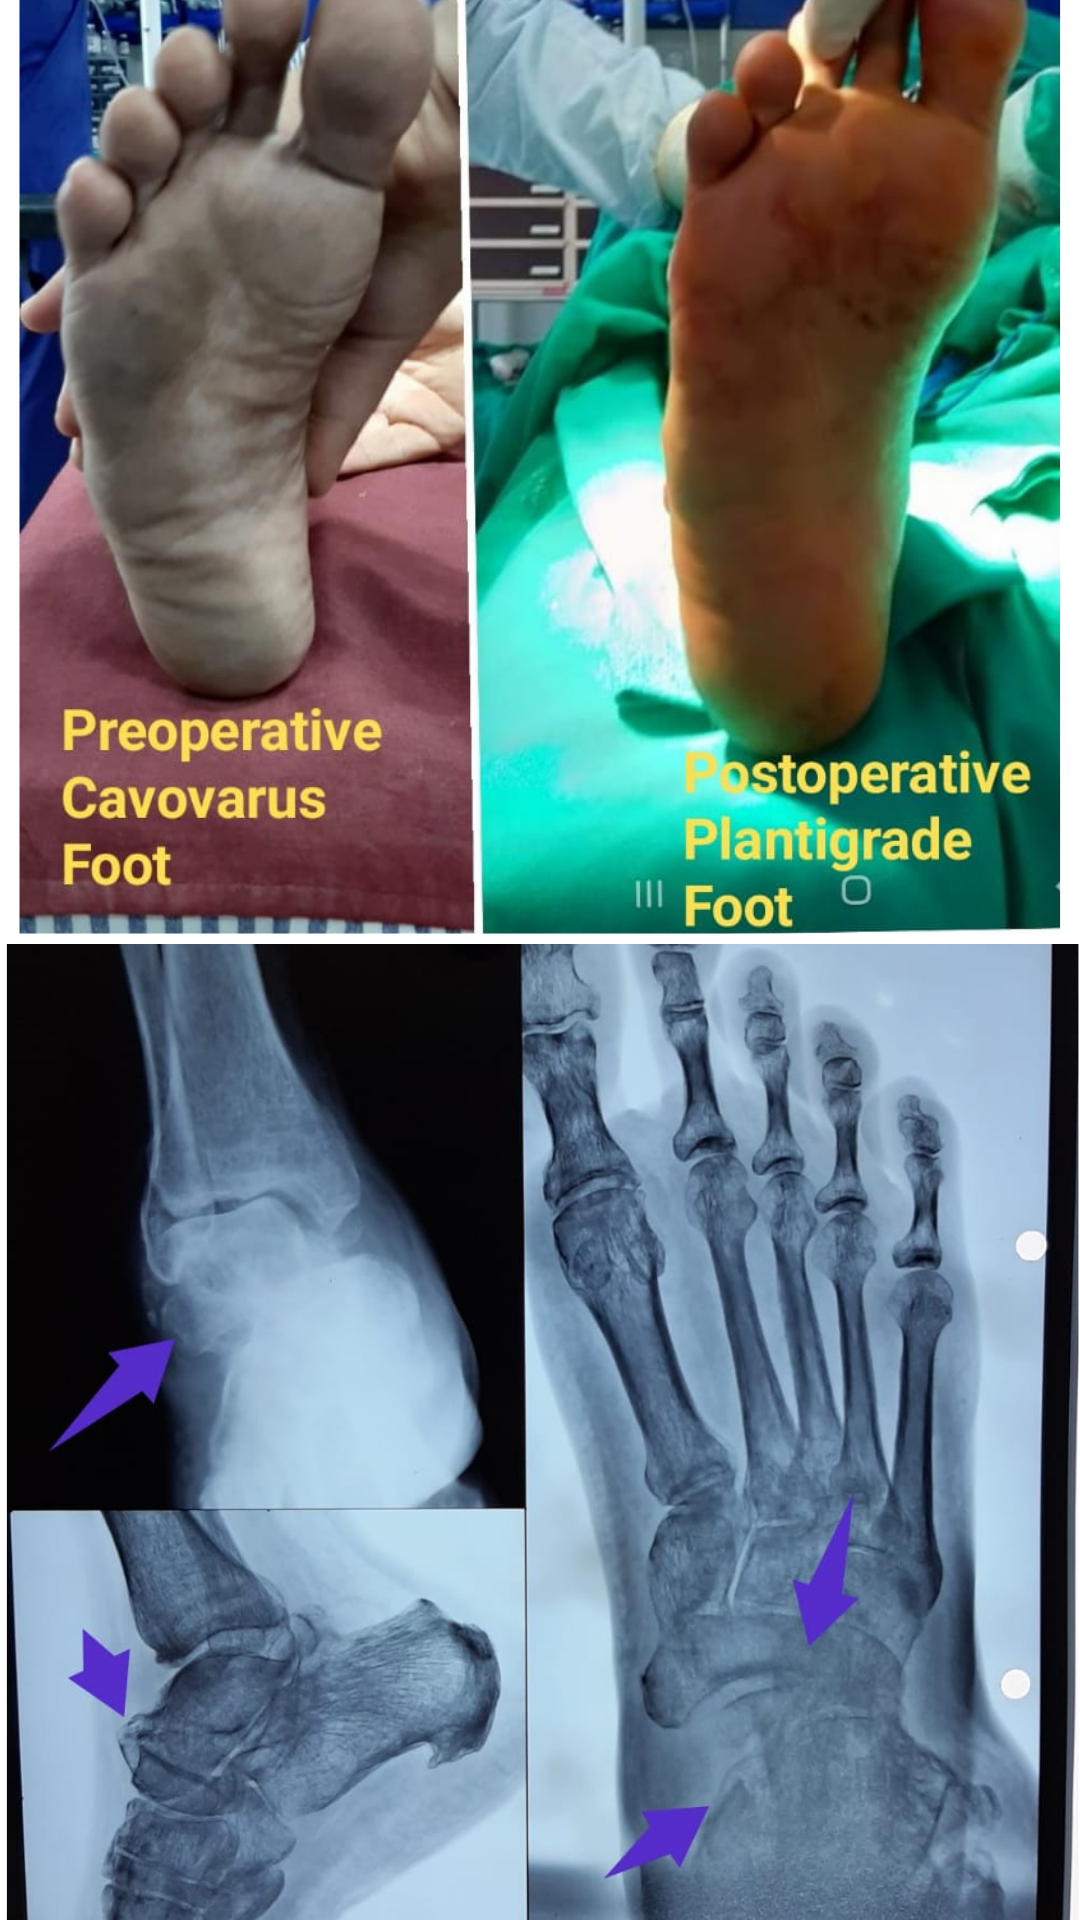

Severe foot deformity- Cavovarus foot- Dr Girsh Motwani

Severe foot deformity- Cavovarus foot- Dr Girish Motwani

This is the case of 24 years / male who has undergone simple tibia interlock nailing following diaphyseal fracture in 2017   Unfortuna...